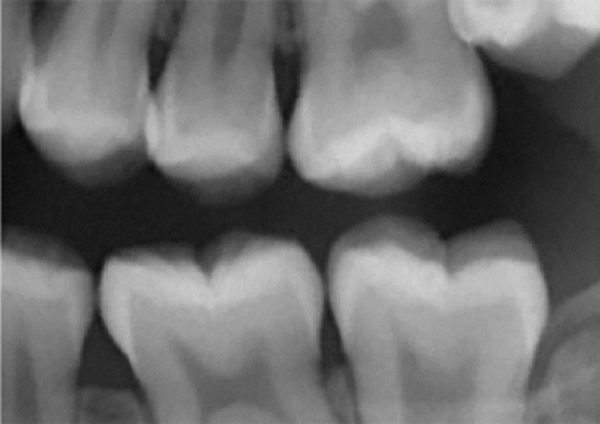

Figure 1 Traditional intraoral bitewing showing limited field of view (Fig 1) compared to the expanded view possible using CBCT (Fig 2).

Figure 1

Figure 2 Traditional intraoral bitewing showing limited field of view (Fig 1) compared to the expanded view possible using CBCT (Fig 2).

Figure 2

CBCT can also be used in this same manner to perform an even more common task, bitewing images, which are clinically indicated as often as every 18 to 24 months. For hygiene patients whose films require updating, CBCT offers a “patient-friendly” approach. Given that these films, which are usually performed intraorally, are often taken on an hourly basis in the typical general practice, the technology can be well utilized while also increasing comfort and satisfaction among patients. In addition, due to the expanded field of view that can be achieved with these extraoral CBCT images, they can often be more diagnostically valuable than images produced with an intraoral sensor (Figure 1 and Figure 2).